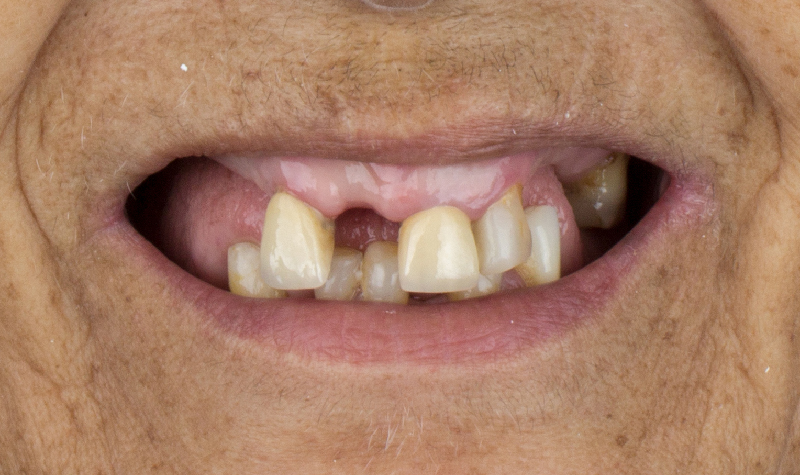

Rehabilitación oral total con prótesis inferior sobre implantes y coronas superiores.